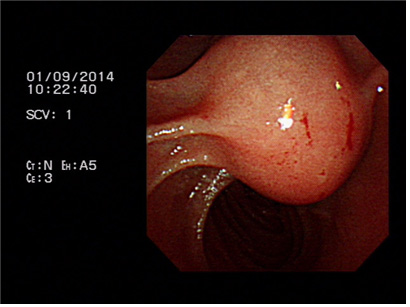

증례 2. 황달로 내원하여 유두부 결석 진단하에 담도내시경을 이용한 결석 제거술 시행 1예.